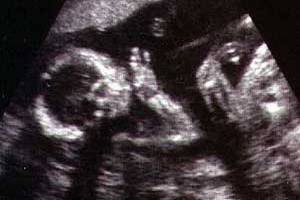

УЗД тепер робиться нечасто, термін другого скринінгу позаду, а останнє планове УЗД ще не скоро. Однак, за необхідності обстеження ще призначається. Ваш малюк вже такий великий, що не може повністю поміститися на екрані УЗД апарату, але частини тіла легко помітні.

УЗД дозволяє визначити вагу плода, його розміри і положення в матці, оцінити стан і місце прикріплення плаценти, кількість навколоплідних вод.